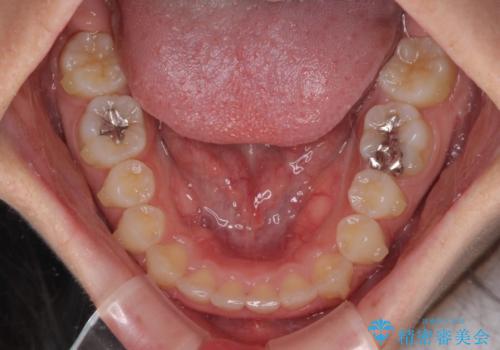

前歯のデコボコと突出感 インビザラインによる矯正治療

- 上下前歯のデコボコと、上顎前歯の突出感を気にして来院された患者様です。

インビザラインによる上下歯列の側方拡大と後方移動、IPR(歯と歯の間を削る)にるスペースの獲得により歯列を整えることとしました。

毎日22時間以上しっかりとマウスピースを装着していただいたので、スムーズに治療が進みました。歯と歯の間を削ることでうまくスペースコントロールでき、1年強で終えることができました。